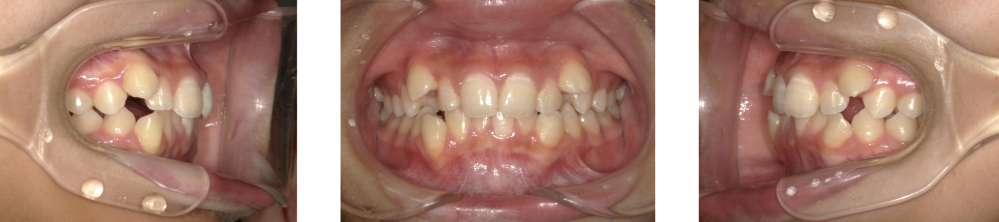

Before Photo

Before

After Photo

After

主訴

ガタガタ、八重歯が気になる。

治療期間

1年11ヶ月

料金

相談料0円、検査料33,000円、動的矯正治療費990,000円、保定装置料5,500円×2枚(必要枚数)

治療概要

上下の個々の歯の大きさに対して、上下の顎が共に小さく、歯が並ぶ余地が不足したために、改善には、上下左右の第一小臼歯を抜歯して空隙を作り、叢生を改善した。

矯正での歯の移動のリスクとして歯根吸収、歯肉退縮、歯髄壊死が考えられます。

保定装置の装置を怠ると隙間が生じてくる可能性があります。